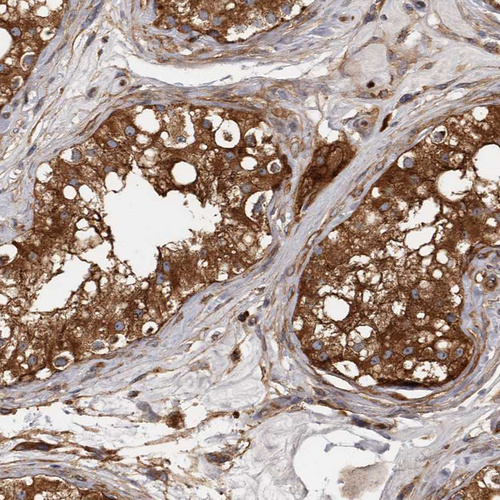

Immunohistochemistry analysis in human testis and liver tissues using HPA028448 antibody. Corresponding ENAH RNA-seq data are presented for the same tissues.